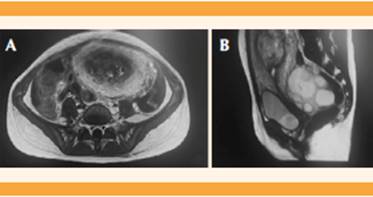

Se estudió el caso detenidamente junto a la Unidad de Oncología Pediátrica y se concluyó que se trataba de una mola invasiva, por lo que se propuso el legrado diagnóstico-terapéutico y plantear una pauta de poliquimioterapia, en virtud de sus características de alto riesgo, como el tamaño tumoral, la cifra de β-hCG y las metástasis pulmonares. La resonancia magnética craneal (Figura 4) no reportó hallazgos de interés y la pélvica (Figura 5) confirmó la invasión miometrial porque se identificó un límite impreciso entre el tumor y el miometrio en la cara posterior, asociado con una distorsión de la anatomía, con hiperrealce miometrial; se descartó la enfermedad local extrauterina.

Figura 5 Imágenes A y B. Resonancia magnética pélvica. Con el contraste se observan focos de realce tumoral que sugieren enfermedad activa. Hay límites imprecisos entre el tumor y el miometrio, en su cara posterior, con distorsión asociada de la anatomía e hiperrealce miometrial en fase inicial del estudio dinámico, con contraste que traduce invasión miometrial.